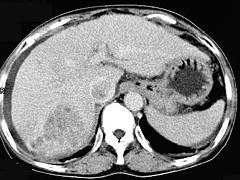

问题 女性,55岁,曾患乙肝,肝硬化多年,右上腹胀痛1月余,CT检查如图所示,最可能的诊断是 ( )

选项 A.肝硬化腹水、下腔静脉血栓形成 B.肝硬化腹水、胆管细胞癌 C.肝硬化腹水、肝癌并下腔静脉癌栓 D.肝硬化腹水、肝脓肿 E.肝硬化腹水、肝血管瘤

答案 C